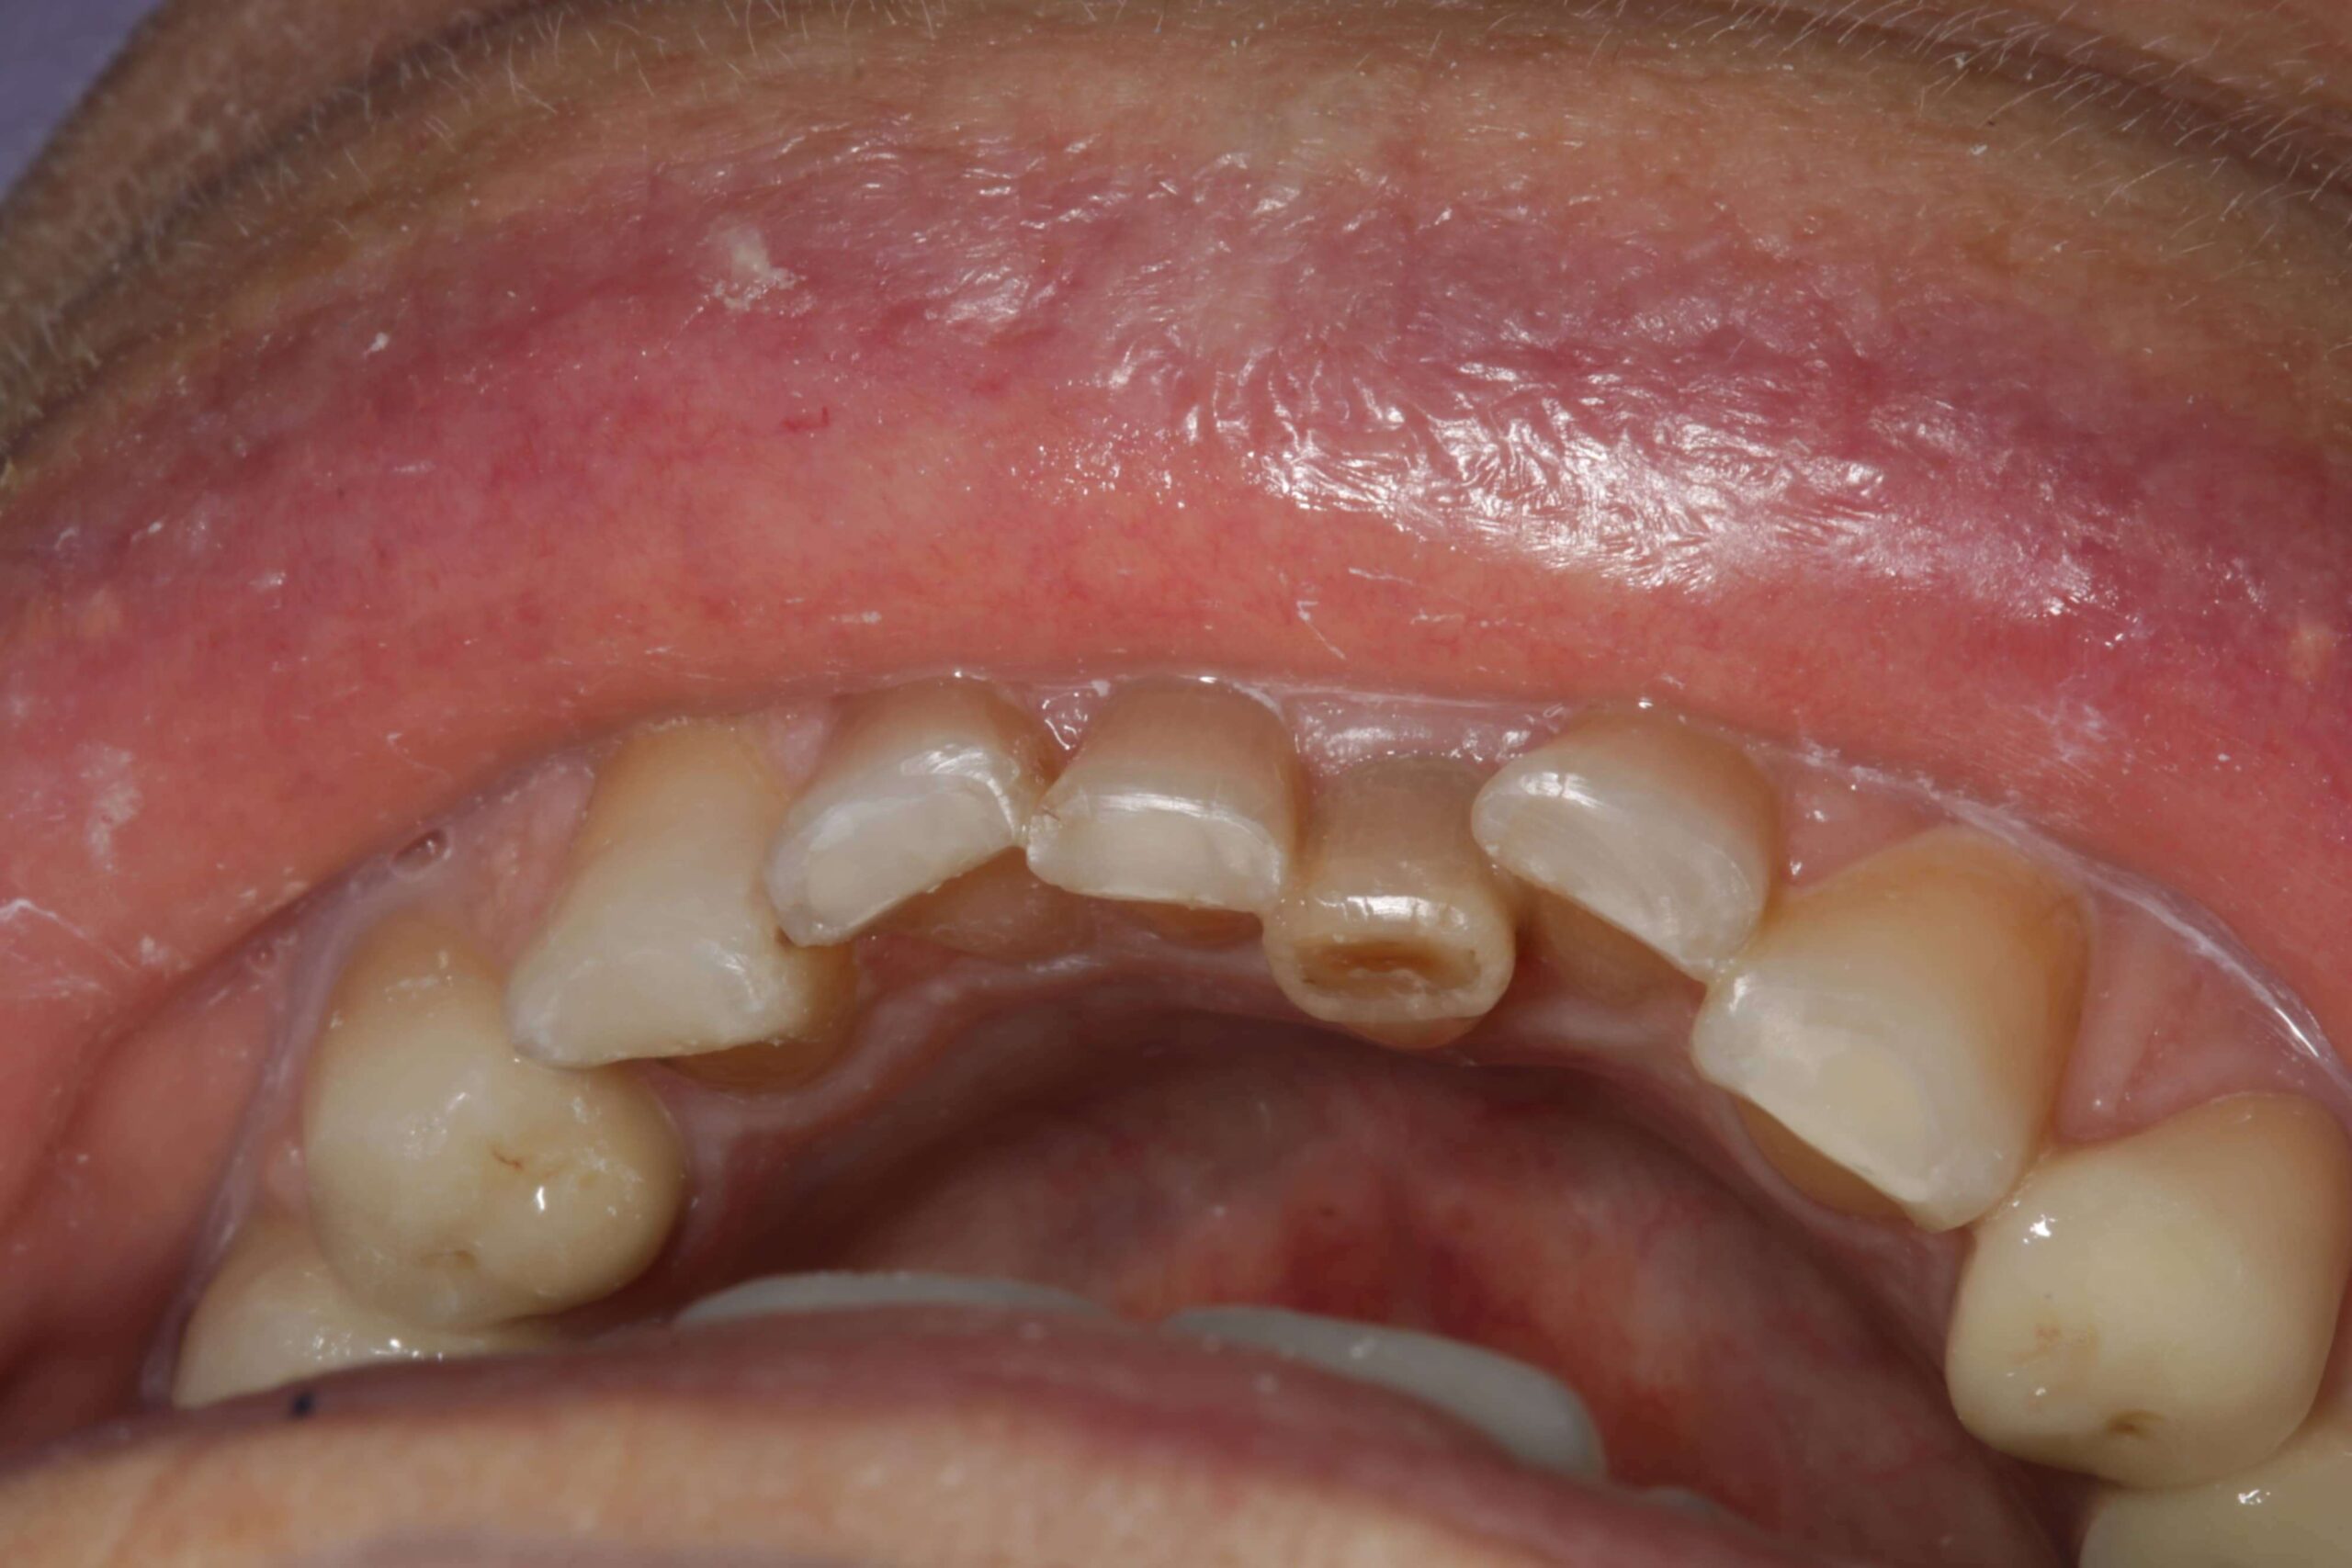

2. Fogászati eredetű fájdalmak

A fogak és az állkapocs közeli kapcsolatban állnak egymással, így számos fogászati probléma válthat ki állkapocsfájdalmat:

- Fogfájás: például gyökércsatorna-gyulladás vagy tályog

- Foghúzás utáni szövődmények: gyulladás, fertőzés, száraz fogmeder

- Bölcsességfog: különösen az előtörés során vagy a ferdén nőtt bölcsességfogak nyomása esetén alakulhat ki állkapocscsont fájdalom

- Nem megfelelően kialakított fogpótlások: rosszul illeszkedő koronák, hidak vagy kivehető pótlások hosszú távon megváltoztathatják a harapási viszonyokat, túlterhelhetik az állkapocsízületet, és funkcionális egyensúlyzavart idézhetnek elő. Ez gyakran vezet feszüléshez, rágás közbeni fájdalomhoz vagy ízületi kattogáshoz.

Fogászati kezelés

- Fogtályog, szuvas fog, gyulladás vagy foghúzás utáni komplikáció esetén antibiotikumos kezelés, gyökérkezelés vagy sebészi beavatkozás lehet szükséges